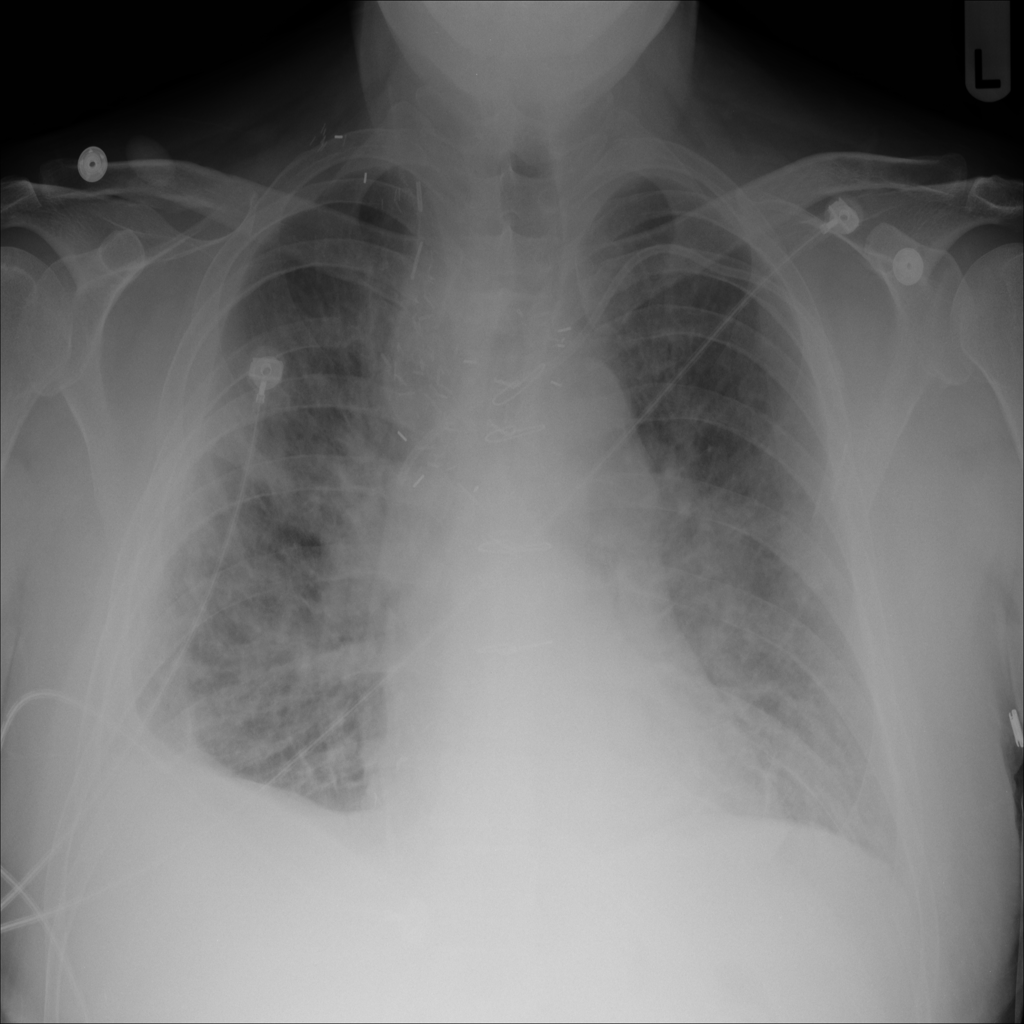

Mass

A mass is a larger focal opacity or lesion seen on the image. It is a descriptive finding that can have several causes and usually needs more imaging or clinical context to characterize.

PAT-4639 · IMG-024Mass

PAT-4639 · IMG-024

AP